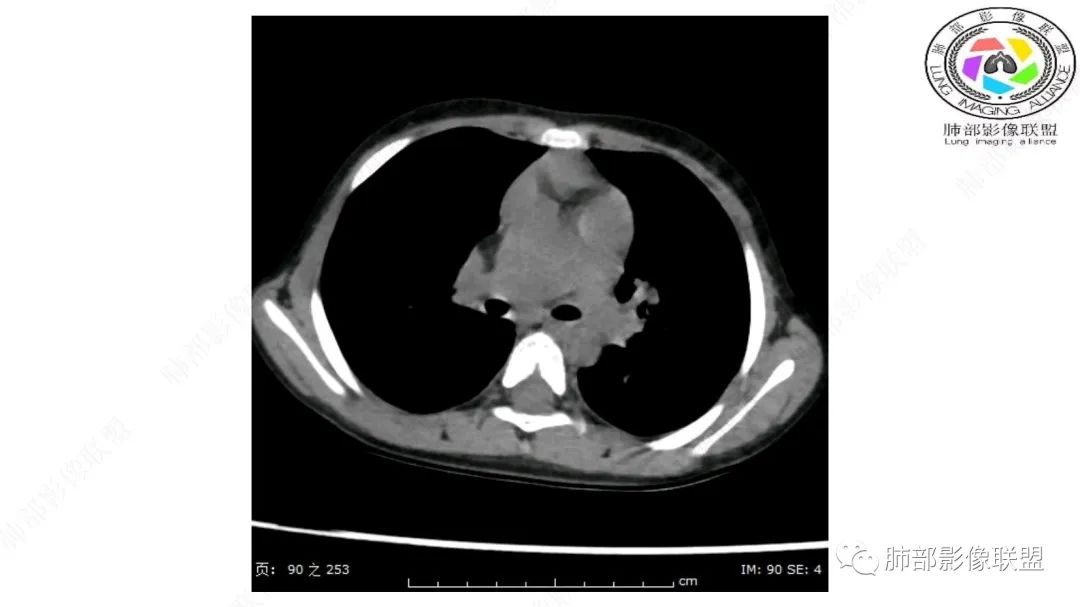

右上纵隔混杂密度肿块,边缘光整,与纵隔分界清,其内多发脂肪密度,增强无明显强化,其内血管穿行,考虑纵隔脂肪母细胞瘤,鉴别畸胎瘤,脂肪肉瘤。

三岁小儿,右侧纵隔巨大脂肪密度肿块,肺动脉穿行其中,密度欠均匀,未见明确实性成分,纵隔脂肪母细胞瘤,冬眠瘤鉴别纵隔脂肪增多症(多弥漫对称)。

纵隔畸胎瘤,右前上纵隔团状脂肪密度?粘液样密度为主病变,病灶软边缘有分叶,内可见分隔,增强后血管穿行。3岁。考虑纵隔脂肪母细胞瘤,鉴别畸胎瘤。

右肺门上方,位于纵隔胸膜旁见巨大肿块,脂肪为主混合密度,内见细小血管影,肿块最大长径与纵隔胸膜平行,包绕右肺上叶肺动脉,右肺上叶及纵隔结构推压,无侵蚀破坏,良性肿瘤,起源纵隔胸膜血管平滑脂脂肪瘤。

病灶属于交界区,主体位于肺内,占位效应明显,前方突入胸壁,胸腺受压变形,胸膜显示欠清楚;病灶包绕上叶肺动脉;似乎有体动脉供血。符合肺内的点:包绕上叶肺动脉分支;符合纵隔的点:前方似乎突入胸壁,与胸腺关系比较密切,但是与上腔静脉的关系提示病灶不支持纵隔来源,前纵隔的常规会将上腔静脉受压后移、外移,这是不符合的。

手术记录:见右肺上叶肿物,肿物与右肺上叶关系密切。与纵隔无粘连,逐步分离肿物,见肿物大小约6cm*5cm,边界清楚,于右肺上叶粘连,边界清楚,肿物包绕右肺上叶血管及支气管。超声刀逐步游离肿物,完整切除肿物,右肺上叶肺组织无破溃,表面无出血。

1.右上肺-纵隔交界区巨块影,主体位于右肺一侧,紧贴胸腺、头臂干、右锁骨下动脉、上腔静脉、奇静脉等,不能分离,但病灶整体边界清楚。注意上述相邻腔静脉等结构未见受压变形,纵隔亦未见明显向左推移,至少提示两点:

1)病灶相当柔软。

2)位于纵隔内或纵隔胸膜的可能性较小,因为受纵隔胸膜反作用力影响不明显。

2.肺动脉穿行也许是肺内来源最重要支持点!

CT扫描对脂肪类肿瘤常有独到价值。肿块孤立、边界清楚,未见周围浸润,较均匀脂肪样低密度,高度提示为良性!

发生于成人为脂肪瘤表现,婴幼儿自然会想到脂肪母细胞瘤。两者生物学行为并无本质区别。